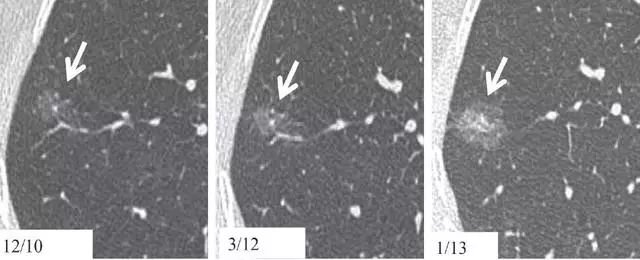

9. 相隔 2 年的结节渐进表现

图 9 右肺下叶层厚 1 mm 的 CT 横断面图像,(a)显示边界清楚的 6 mm 大小毛玻璃样结节(箭头)。(b)2 年多后获得的图像,显示结节大小略有增加(箭头)。与相邻血管结构关系的轻微变化,证实了这一结果。这种微小进展只能通过层厚 1 mm 的连续扫描来发现。此类图像符合原位腺癌或微浸润腺癌表现,建议继续进行年度随访。